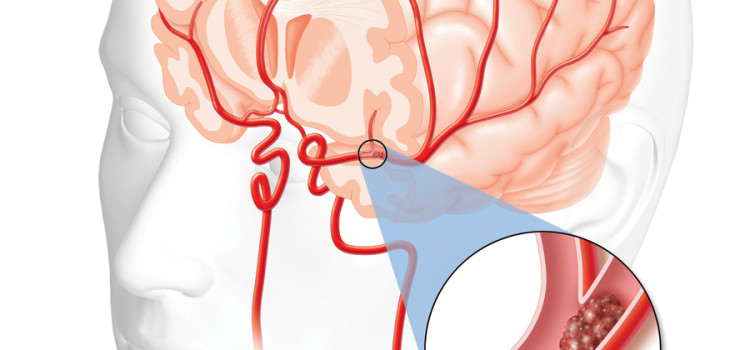

Ишемический инсульт левой стороны: симптомы и реабилитация